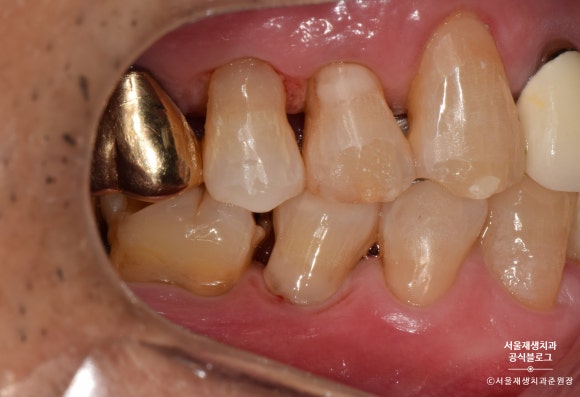

글라스아이오노머로 치경부마모증 치료하기

레진에 비해 자연스러움이나 수명은 약간 부족하지만,

저렴한 가격에

치경부마모증의 치료를 위한

최소한의 자격요건을 갖춘 기특한 재료입니다.

글라스아이오노머로 치료를 시작해보겠습니다.

며칠 후 글라스아이오노머 치료를 위해 다시 방문해주셨습니다.

그 사이 감쪽같이 아문 잇몸이 보이시나요?^^

글라스아이오노머를 이용한 치료도

레진과 마찬가지로 치아의 표면을 깨끗하게 소독하는 것으로 시작합니다.

글라스아이오노머를 위한 전처리제를

치아표면에 도포합니다.

글라스아이오노머를 치아 표면에 도포합니다.

밀가루 반죽같은 것을 기구를 대고 꾹~ 눌러주거나,

시린지 형태로 된 제품으로 짜넣는 방법 등이 있습니다.

5분 정도의 시간이 지나고

글라스아이오노머가 제법 단단해졌습니다.

글라스아이오노머의 표면을 부드럽게 다듬어봅니다.

레진과 비교했을 때 약간 혼탁한 색감, 부자연스러운 느낌은 있지만,

후방치아 치료용으로는 손색이 없습니다^^